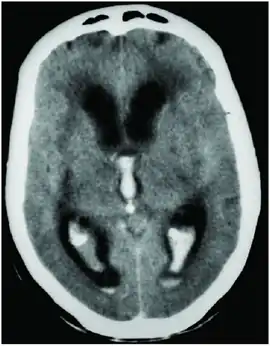

CT scan showing spontaneous intracerebral hemorrhage with bleeding in the third and both lateral ventricles and hydrocephalus[1] | |

Prognosis is very poor when IVH results from intracerebral hemorrhage related to high blood pressure and is even worse when hydrocephalus follows.[1] It can result in dangerous increases in ICP and can cause potentially fatal brain herniation.[1] Even independently, IVH can cause morbidity and mortality. First, intraventricular blood can lead to a clot in the CSF conduits blocking its flow and leading to obstructive hydrocephalus which may quickly result in increased intracranial pressure and death.[15] Second, the breakdown products from the blood clot may generate an inflammatory response that damages the arachnoid granulations, inhibiting the regular reabsorption of CSF and resulting in permanent communicating hydrocephalus.[2][15]